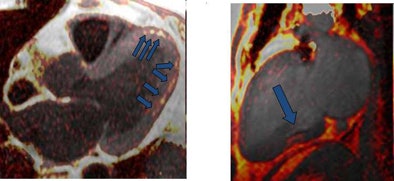

| Above, four-chamber, three-chamber, and short-axis images of a patient with fat deposition in segments of myocardial infarction. Precontrast fat-water separation imaging shows midwall fat deposition that is hyperintense in fat images and hypointense in water images. Late gadolinium-enhanced (LGE) infarct imaging shows an apical-septal chronic myocardial infarction. Below, fat-water separation imaging color overlay. Colored fat displayed on grayscale water images from two patients with chronic myocardial infarctions. Arrows point to midwall fat deposition. Images courtesy of Dr. James Goldfarb. |

Fat deposition was seen in 68% of patients in areas of chronic MI. Patients with fat deposition on imaging had larger infarctions (30.0 mL ± 15.1 [standard deviation] versus 14.8 mL ± 6.1; p = 0.002), less wall thickening (2.3% ± 20.0 versus 37.8% ± 34.4; p = 0.003), and impaired endocardial wall motion (2.9 mm ± 2.0 versus 5.8 mm ± 2.6; p = 0.007) compared to normal patients, the group reported. In addition, the volume of fat deposition correlated with infarct volume, LV ejection fraction, LV end-diastolic volume index, and LV end-systolic volume index.

"Since fat deposition was found solely in myocardial segments with or directly adjacent to MI, one might infer that LV MI is a precursor to LV myocardial fat deposition," Goldfarb and his team wrote, adding that serial imaging over several years would be necessary to test the hypothesis. "We also found that fat deposition was predominately midmyocardial or midepicardial, whereas results of prior autopsy and CT studies suggest that fat deposition almost always affects the subendocardium."

"There is a high prevalence of fat deposition in healed MI. It is associated with postinfarction characteristics including infarct volume, LV mass, wall thickness, wall thickening, and wall motion," the authors wrote.